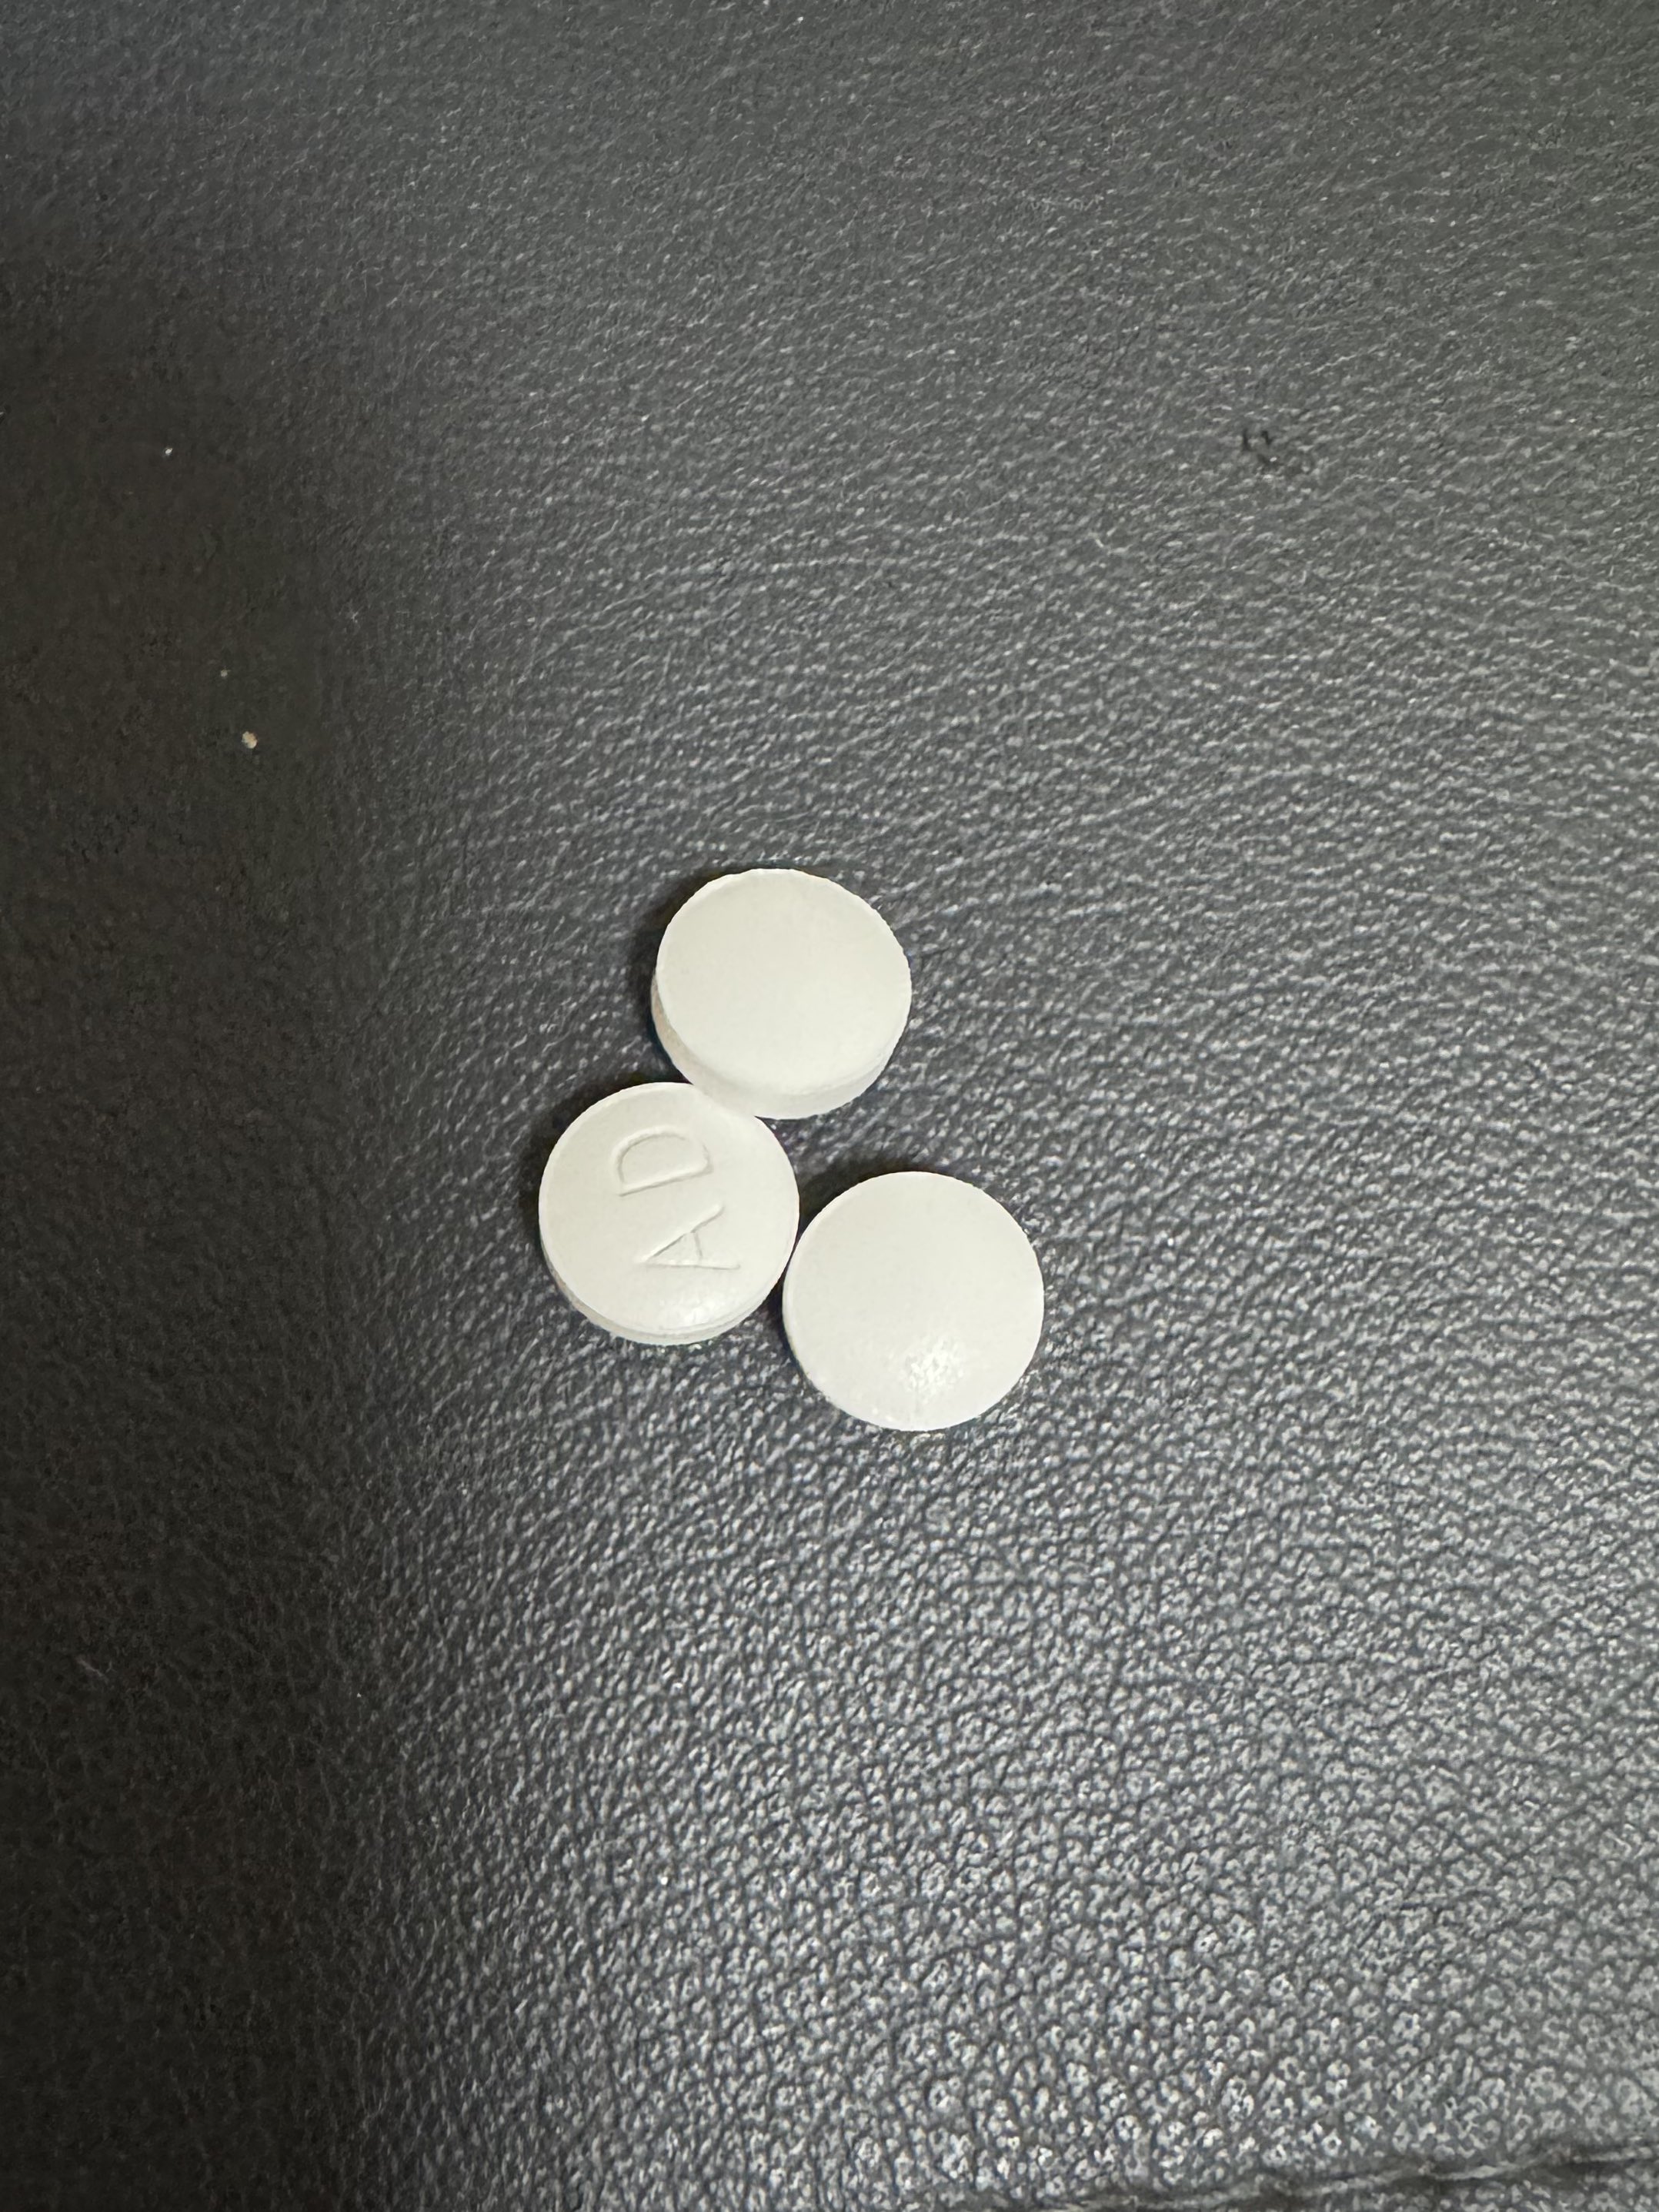

金刚烷胺会对神经系统造成长期/不可逆的影响

首先多巴胺系统

金刚烷胺作为多巴胺释放促进剂,在长期使用或过量下可能导致:

-DA系统适应性衰竭(Receptor downregulation)

-药源性多巴胺枯竭综合征:表现为认知退化、动机缺失(apathy)、情绪迟钝等。

NMDA

虽然金刚烷胺是弱NMDA拮抗剂,但长期使用可能导致:

-突触可塑性损伤(LTP/LTD受阻)

-情景记忆下降、学习能力减退

-焦虑、攻击行为升高

-神经元代谢负荷增加,增加兴奋毒性风险

金刚烷胺提高兴奋性毒性(NMDA活性失衡、多巴胺代谢紊乱),与致幻剂合用或交替用药会:

-加剧皮层-边缘系统的不稳定性(例如海马体、前额叶)

-增加精神病风险(psychosis risk)

-导致长期认知损伤与感知畸变的残留症状(HPPD-like states)

另外有导致神经适应性结构改变

动物研究提示,金刚烷胺长期使用可能导致:

-树突棘数量下降

-突触可塑性衰退

-神经炎症因子(如IL-6)升高,为不可逆脑损伤打下基础

2025-04-29 11:45:39 UTC

简版

金刚烷胺不但无法提供真正的致幻体验,反而会破坏大脑、干扰神经系统,带来无法逆转的损害。

短期风险:

-幻觉质量差、碎片化,常伴恐惧、迷惑、妄想

-谵妄状态(严重的意识混乱)

-焦虑、失眠、暴躁、攻击性升高

-心跳紊乱、口干、头晕、甚至癫痫发作

长期风险:

-损伤大脑中的多巴胺与谷氨酸系统

-学习能力下降、情绪变平淡、认知迟钝

-增加患上药源性精神障碍的风险

炽烈已极 @AnIncandescence金刚烷胺会对神经系统造成长期/不可逆的影响